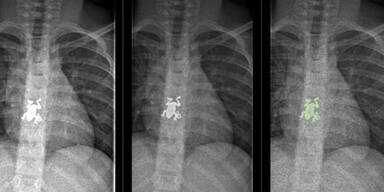

Mädchen hatte Frosch im Hals

Der Frosch war in der Speiseröhre und verursachte starke Schmerzen.

Schreck für ein siebenjähriges Mädchen aus der Schweiz. Die Kleine wurde mit starken Schmerzen ins Inselspital in Bern eingeliefert. Dort wurde auf den Röntgenbildern entdeckt, dass sie einen Frosch im hals hatte. Allerdings keinen echten, sondern einen knapp drei Zentimeter großen Schmuckanhänger.

Unter Narkose und mit einer Greifzange konnten die Ärzte den Frosch herausholen. "Trotz der ungewöhnlichen Röntgenbilder war das Mädchen nie in Lebensgefahr“, so  Chefarzt Daniel Garcia zu "20min".